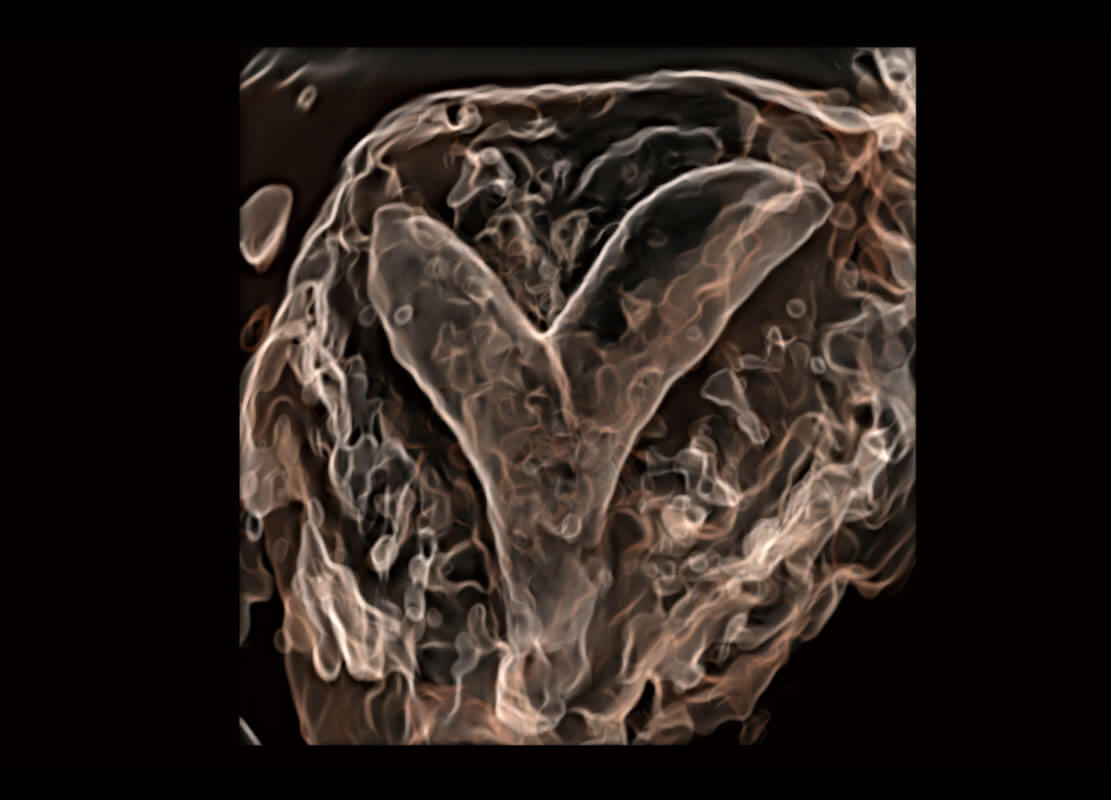

腔內(nèi)三維-宮內(nèi)節(jié)育器

腔內(nèi)三維-光影成像